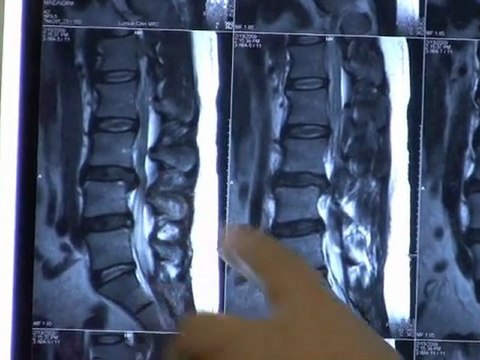

Spinal Decompression For Sciatica, Back & Neck Pain in Wood

bestatlantaspinaldecompression.com Help for Sciatica Back & Neck Pain.How to choose a spinal decompression center. Get a FREE e-book. the truth Spinal Decompression. Dont get ripped off!